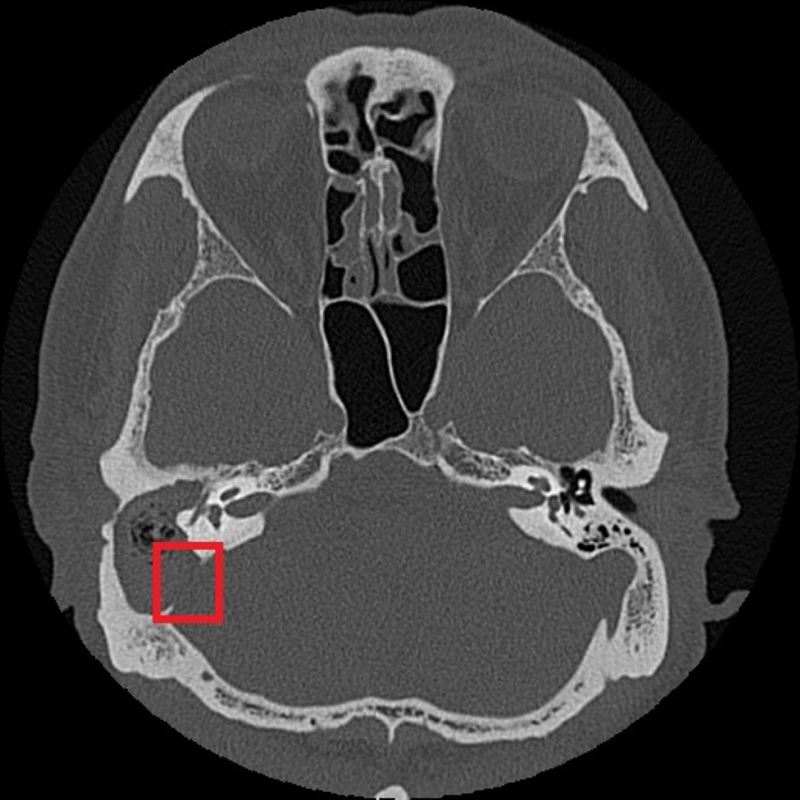

紅框處可見與後顱窩相隔的骨板被膽脂瘤侵蝕。(圖/台北慈濟醫院提供)

台北慈濟醫院耳鼻喉科鄭靜雯醫師檢查後發現,張先生不僅是單純發炎,透過顳骨電腦斷層(CT)一看,確診為「慢性中耳炎併發膽脂瘤」。最駭人的是,這顆瘤雖然是良性,卻具備極強的破壞力,病灶早已侵蝕顱底骨質,甚至壓迫到神經導致臉歪。